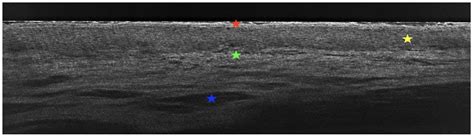

Because the disease state can change, you should view your dental team as your primary partners in health. Regular check-ups are not just for cleaning your teeth; they are essential for conducting an oral cancer screening. A biopsy might be required if the clinical appearance of a lesion changes or if it does not respond to standard treatment protocols. Never skip these appointments, as early detection of any tissue transformation offers the best possible prognosis.